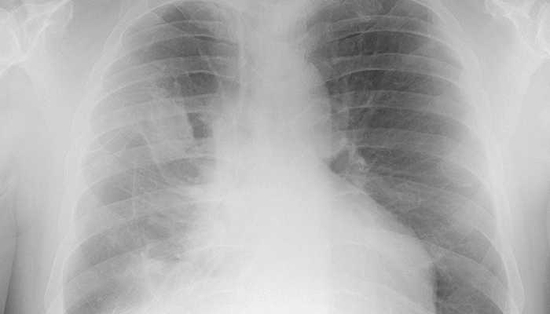

而之所以会出现“白肺”,首先与肺部影像学的呈像原理有关。焦雅辉介绍,肺部是由肺泡组成的,肺泡里面充满空气,进行CT或者X线检查的时候,射线穿过肺泡,影像表现是黑色区域;但是,当肺泡里出现炎症或感染,有渗出液和炎性细胞的时候,肺泡就被这些渗出液和炎性细胞所填充,射线就穿不透,在影像学上出现白色区域。白色区域反映出来的是渗出物的影像学表现,并不是肺脏组织实体变成了白色。

图片来源:视觉中国

焦雅辉强调,并不是说只要肺部出现了炎症就都是白肺,白肺是比较严重的肺炎表现,这个阶段患者会出现低氧血症或呼吸窘迫。随着渗出液的吸收、炎症的消退,白肺的表现也会逐渐消退,肺部的影像学表现会逐步恢复为黑色区域。